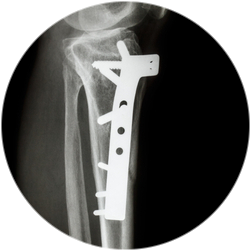

Установка металлической конструкции с помощью накостного или интрамедуллярного остеосинтеза, соединение костей снаружи с помощью аппарата Илизарова. Тип операции зависит от тяжести повреждения.